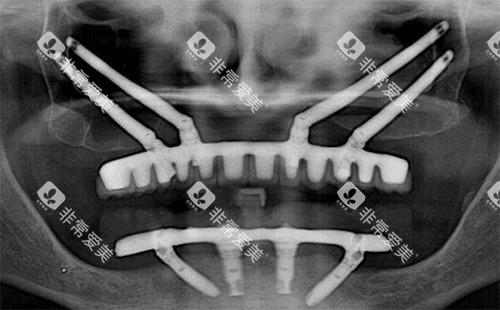

门诊部的特色项目众多,其中穿颧穿翼种植牙技术是一大亮点。

穿颧穿翼种植牙适用于一些骨量重度不足的患者,无需大量植骨就能完成种植,大大缩短了治疗周期,减轻了患者的痛苦。

此外,研究人潘蛟南医生擅长的即刻种植、即刻修复、即刻负重种植牙技术也备受瞩目。

这些技术可以让患者在较短时间内改善牙齿的功能和美观,减少多次就诊的麻烦。

同时,上颌窦植骨术、神经避让术、狭窄骨头种植手术等也是该门诊部的特色项目,展现了其在复杂口腔种植领域的可靠实力。

技术优势:门诊部拥有较高的种植牙技术,如前面提到的穿颧穿翼、即刻种植等。

即刻种植技术可以在拔牙后立即植入种植体,减少了患者的等待时间,同时也降低了牙槽骨吸收的风险。